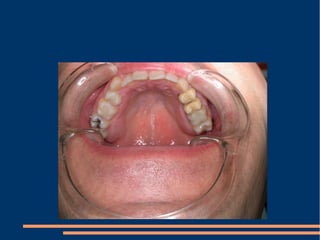

!!! A simple aesthetic treatment PPT